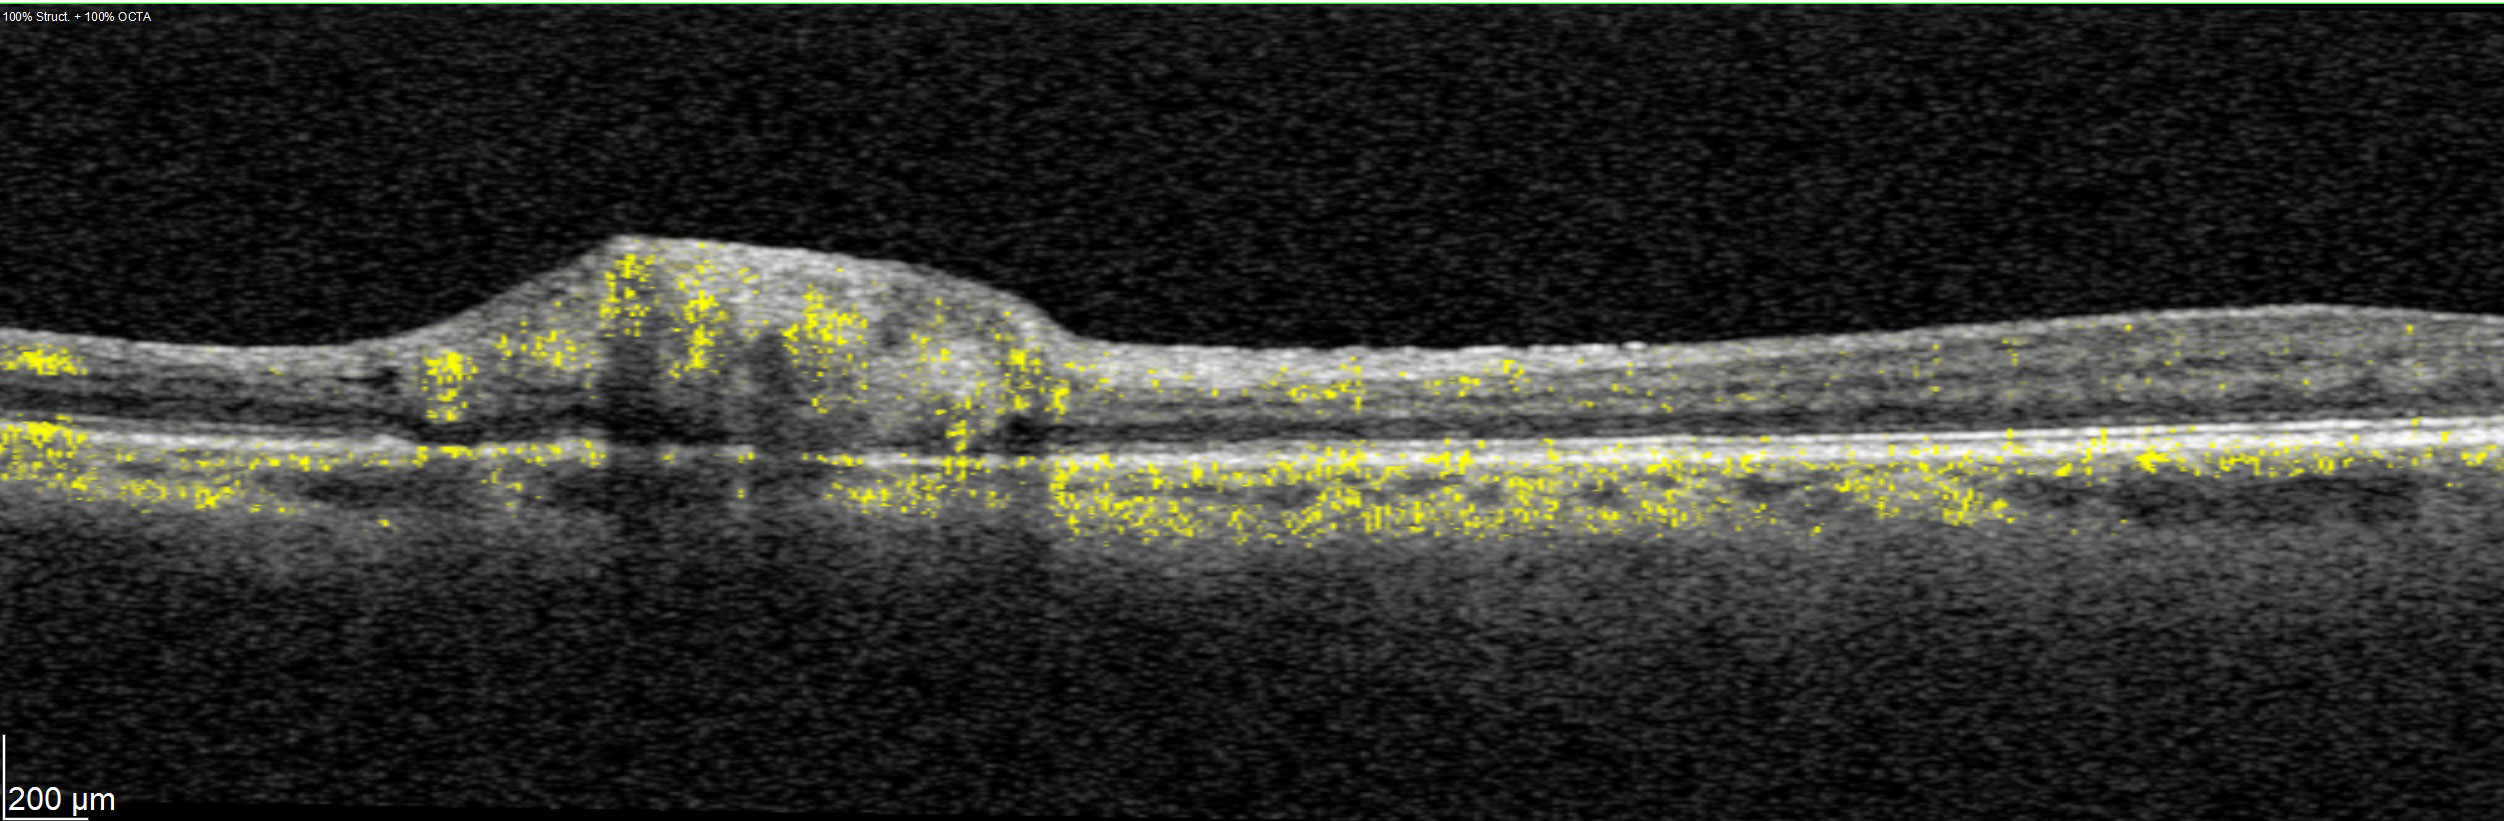

Offering the ideal speed-quality ratio for OCTA, 125 kHz allows you to increase your throughput without any clinically relevant loss in image quality in comparison to the current 85 kHz scan speed. The fast acquisition of images allows for visualization of flow, even in miniscule vessels, while minimizing artefacts, resulting in sharp and detailed images of the capillary network. Additionally, you can decrease chair time when you speed up acquisition with the Glaucoma Module Premium Edition in your glaucoma workflow, if applicable.

SPECTRALIS with SHIFT technology and 125 kHz scan speed empowers you to offer customized diagnostic OCTA imaging of both the retina and the optic nerve head to meet the needs of each individual patient – or adjust to 85 kHz if your patient’s condition requires longer light exposure.

125 kHz – A fast scan speed for improved workflow and high OCTA image quality.